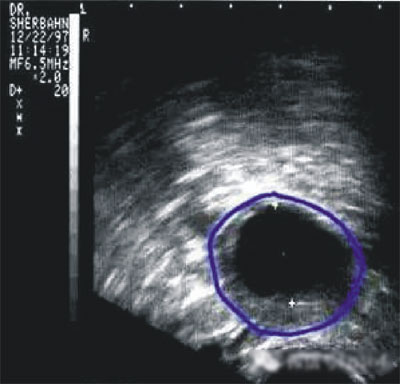

第三步:排卵監(jiān)測(cè)

常用的監(jiān)測(cè)排卵方法有基礎(chǔ)體溫測(cè)定(BBT)、陰道B超監(jiān)測(cè)排卵、血清性激素測(cè)定等。

(圖:排卵監(jiān)測(cè))

陰道B型超聲動(dòng)態(tài)監(jiān)測(cè)卵泡的發(fā)育及排卵,是監(jiān)測(cè)排卵最準(zhǔn)確可靠的方法。通過(guò)陰道B超檢查可以了解子宮及雙側(cè)附件(卵巢和輸卵管)區(qū)的基本情況,測(cè)定卵巢內(nèi)的竇卵泡計(jì)數(shù),評(píng)估卵巢儲(chǔ)備功能,動(dòng)態(tài)監(jiān)測(cè)排卵。